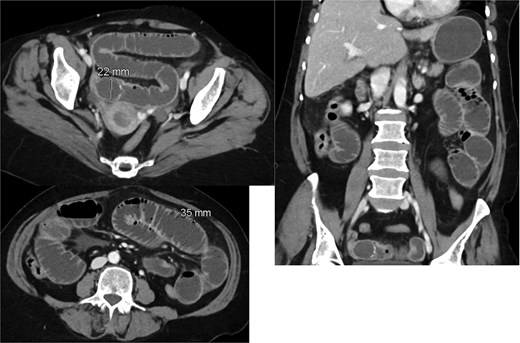

A CT scan of the abdomen revealed (Fig. 1):

A thickened gallbladder with a cholecystoduodenal fistula

A 22-mm gallstone impacted in the distal ileum causing high-grade small bowel obstruction

No signs of bowel ischemia, pneumoperitoneum, or intra-abdominal collections

No evidence of diverticulitis

Contrast-enhanced CT scan of the abdomen and pelvis showing the small bowel loops are dilated reaching up to 35 mm. There is a transition zone with 22 mm gallstone in the distal ileum with distally collapsed ileal segments and collapsed large bowel loops representing high-grade obstruction. The gallbladder appears irregular with thickened wall and significant surrounding fat stranding. There is a fistula between the gallbladder and the second part of the duodenum.

Based on these findings, the diagnosis of gallstone ileus secondary to a cholecystoenteric fistula was made.